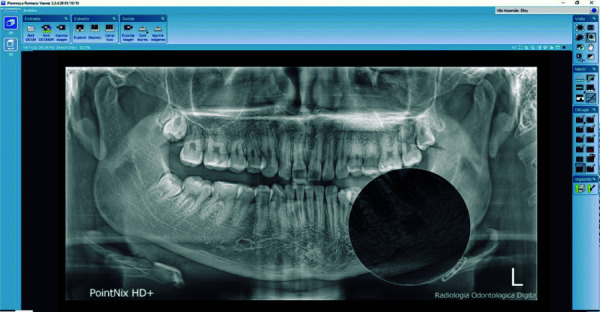

Objective: The objective of this study was to determine, describe and identify the prevalence of radiopaque images compatible with idiopathic osteosclerosis in digital panoramic radiographs taken in patients between the ages of 18 and 50.

Materials and methods: The study design was descriptive, cross-sectional and retrospective. The sample consisted of 500 digital panoramic radiographs taken between January 1, 2016 and December 31, 2018, in the target population aged between 18 and 50 years from Ayacucho - Peru, attended at a private radiological center. The radiographs obtained were analyzed using the Romexis viewer version 5.3 program, and the results were recorded on a data collection sheet. The Chi-square test was used to establish associations among the variables evaluated. A P <0.05 was considered significant.

Results: 500 digital panoramic radiographs were analyzed, showing a prevalence of idiopathic osteosclerosis of 17.4%, of which 12% were female and 5.4% male, and according to age, the presence of idiopathic osteosclerosis was more prevalent in the second decade of life.